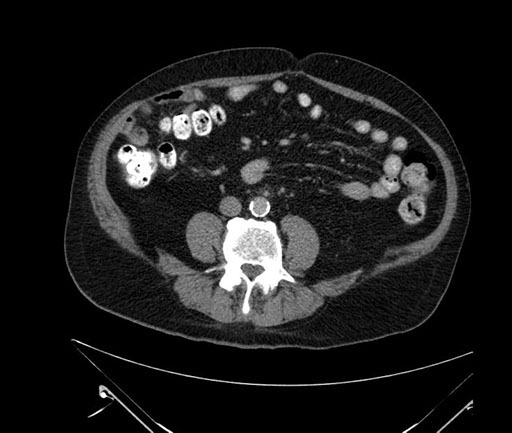

Whipple (pancreaticoduodenectomy) [case 7]

Coronal - stented

Imaging analysis

Based on your CT findings, which issue(s) would give reason for "planned slowing down moment(s)" in this case?

Considering a standard Whipple procedure, what step(s) of the operation would you do differently in this case?